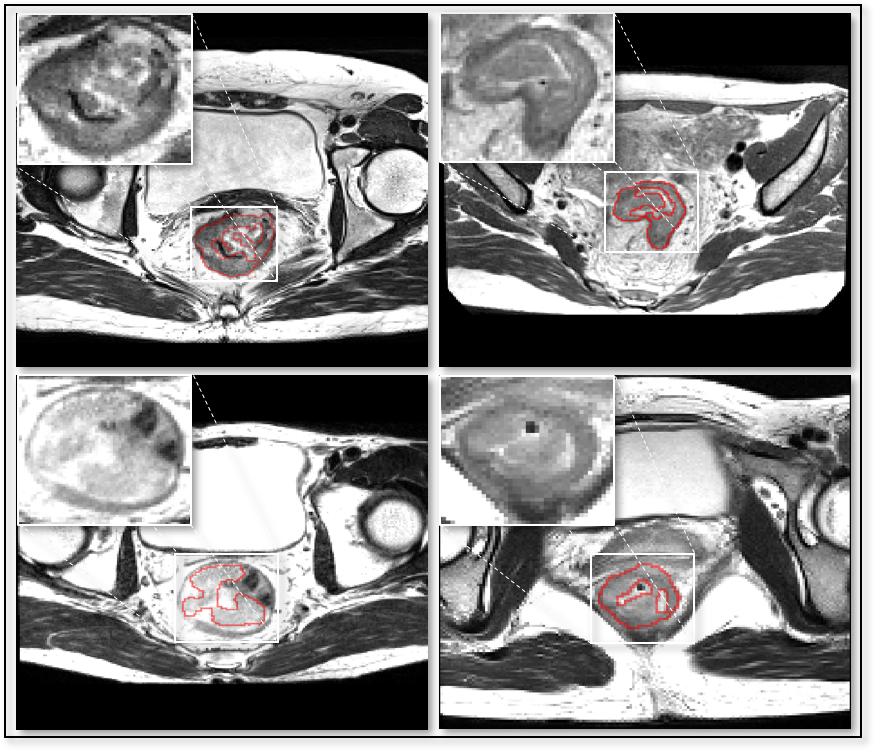

Such demand defines a task of automatic detection and segmentation of the targets from whole 3D image volumes. Compared to processing manually selected RoI patches, the superiority of being fully automatic simplifies the workflow, excludes manual intervention and enables fast processing of large amounts of image volumes. Taking initial works based on super-voxel clustering [3, 4] one step further, deep learning based methods dominate the state-of-the-art of detection and segmentation field. However, deep learning based methods for this task are challenged by following factors: weak intensity specificity, absence of shape characteristic, lacking positional priors (as is illustrated in Fig. 1), class imbalance and long processing time of existing methodologies under inferior GPU or CPU-only deployment environments.

The dataset contains a total of 64 MR images of the pelvic cavity of T2 modality whose ZYX spacings range from mm to mm. Target areas were labeled voxel-wisely by experienced radiologists, and contour labels were automatically generated from the region labels of one-voxel thickness using erosion and subtraction operations. An 3D image has mostly one and up to two RoIs containing cancerous tissues.